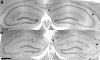

Many viruses, including picornaviruses, have the potential to infect the central nervous system (CNS) and stimulate a neuroinflammatory immune response, especially in infants and young children. Cognitive deficits associated with CNS picornavirus infection result from injury and death of neurons that may occur due to direct viral infection or during the immune responses to virus in the brain. Previous studies have concluded that apoptosis of hippocampal neurons during picornavirus infection is a cell-autonomous event triggered by direct neuronal infection. However, these studies assessed neuron death at time points late in infection and during infections that lead to either death of the host or persistent viral infection. In contrast, many neurovirulent picornavirus infections are acute and transient, with rapid clearance of virus from the host. We provide evidence of hippocampal pathology in mice acutely infected with the Theiler's murine encephalomyelitis picornavirus. We found that CA1 pyramidal neurons exhibited several hallmarks of apoptotic death, including caspase-3 activation, DNA fragmentation, and chromatin condensation within 72 hours of infection. Critically, we also found that many of the CA1 pyramidal neurons undergoing apoptosis were not infected with virus, indicating that neuronal cell death during acute picornavirus infection of the CNS occurs in a non-cell-autonomous manner. These observations suggest that therapeutic strategies other than antiviral interventions may be useful for neuroprotection during acute CNS picornavirus infection.